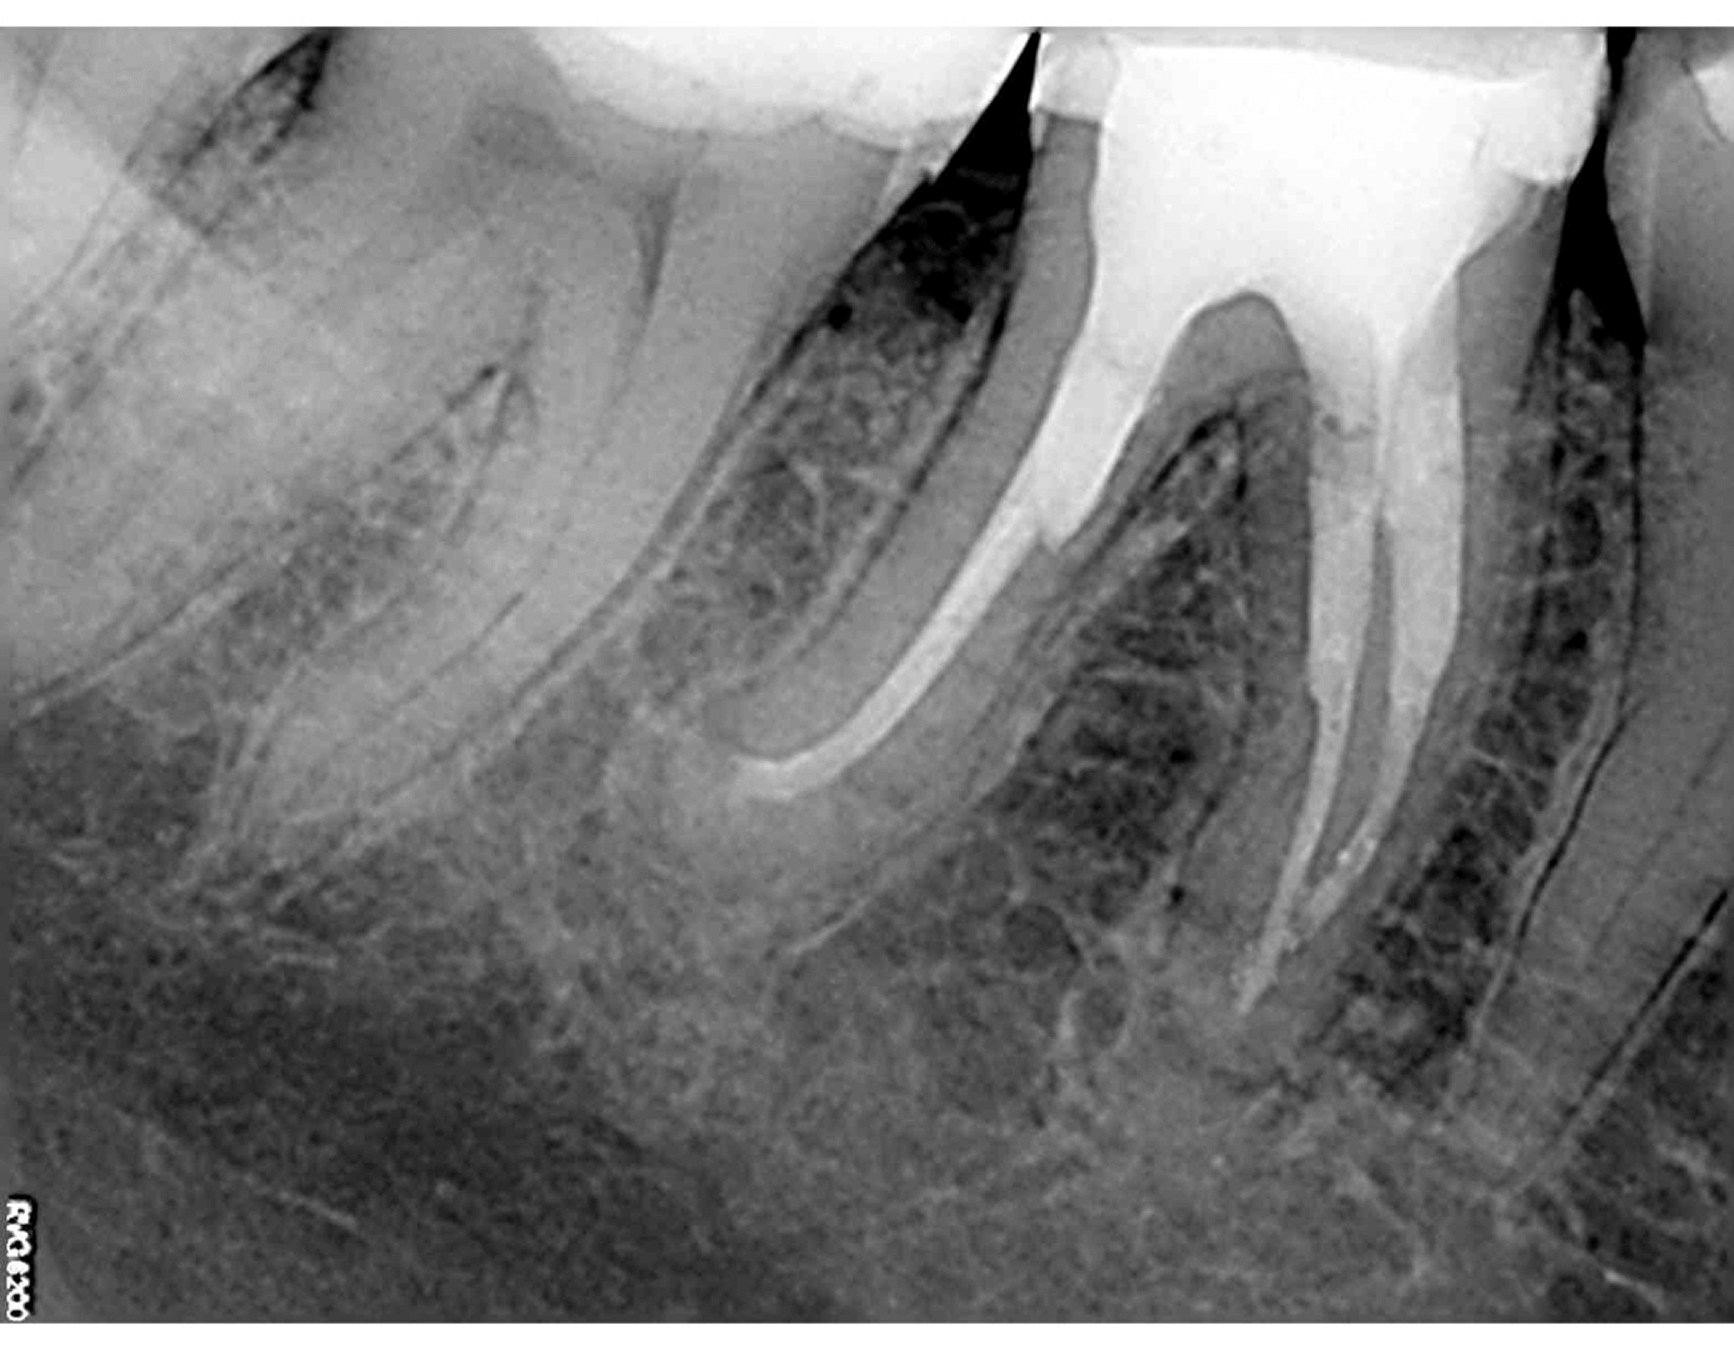

4. The root canals were definitively obturated using gutta-percha and bioceramic sealer, achieving three-dimensional filling confirmed by radiographic control. The tooth was subsequently prepared for and restored with a prosthetic crown, ensuring both functional and aesthetic rehabilitation. (Image 8)